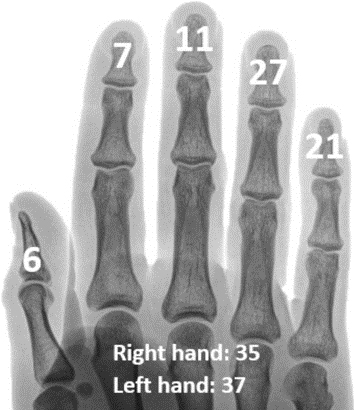

Вероятность появления висячих пальцев на каждом пальце